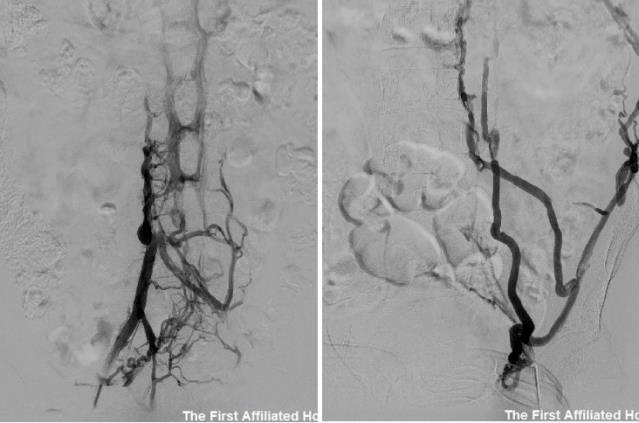

胡志副教授详细了解患者情况后,认为此病例罕见,静脉血栓经开放的卵圆孔栓塞于冠状动脉引起心肌梗死的可能性大,封堵卵圆孔可预防再次出现心、脑等重要脏器致命性栓塞,但由于患者既往存在下腔静脉狭窄伴血栓形成,需评估下腔静脉手术入路;同步下腔静脉造影显示左髂静脉及下腔静脉肝下段血栓形成,管腔狭窄、闭塞,奇静脉开放伴大量侧枝静脉回流建立。

下腔静脉阻塞